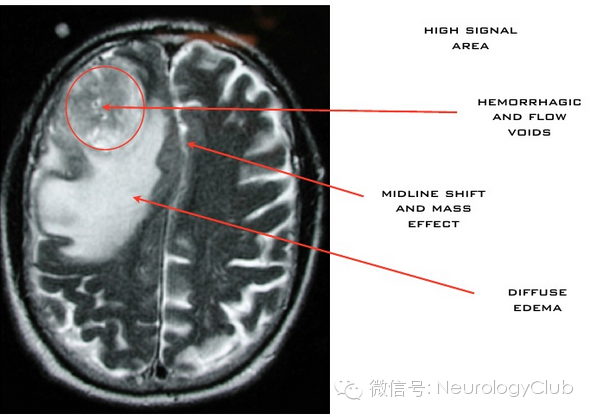

CT显示肿瘤呈边界不清的混杂密度影,常见瘤内出血所致高密度或囊性变、坏死;肿瘤跨胼胝体生长至对侧大脑半球时,呈“蝴蝶征”,水肿和占位效应明显。MRI在一定程度上能够揭示肿瘤的病理改变:T1WI呈不均匀低信号(图 1a),多合并坏死、囊性变或出血性改变;T2WI呈混杂高信号,中心坏死区为高信号,肿瘤生长区周围呈等信号,部分病变与肿瘤周围水肿分界不清,肿瘤内异常血管增生形成线样“流空效应”区(图 1b)。增强扫描肿瘤边缘呈显著对比强化,呈“花环”(ring/rim-enhancing)样(图 1c)、不规则环形、岛形或螺旋形改变;囊变性和坏死区周围肿瘤实质呈特征性“假栅栏征”,即圆形、椭圆形未强化区散在分布在强化区内,类似乳突蜂窝小房。DWI多呈高信号,ADC值明显减低。MRS提示NAA峰降低,Cho升高明显,MI峰较低级别星形细胞瘤低。灌注成像显示,病灶周围和病灶内有多处高灌注区(图 1d),提示大量肿瘤血管生成。胶质母细胞瘤虽具典型影像学特征,但仍需注意与颅内单发转移瘤、间变性胶质瘤、淋巴瘤等肿瘤性病变,以及脑脓肿、结核瘤、脱髓鞘假瘤等非肿瘤性占位性病变相鉴别。

(图8:胶质母细胞瘤周围水肿)